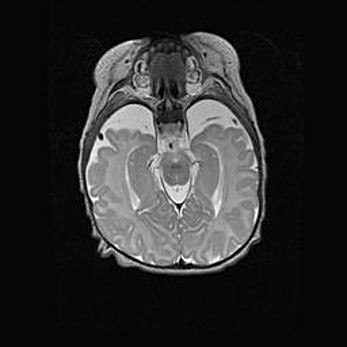

Церебральная ишемия II.

Возраст: 5 дней

Вес: 3400 г

Пол: женский

Окружность головы: 35 см

Срок гестации: 39 недель

Церебральная ишемия – это заболевание, характеризующееся недостаточностью (гипоксией) либо полным прекращением (аноксией) снабжения мозга кислородом по причине закупорки одного или нескольких сосудов. Это приводит к  что метаболическим расстройствам различной степени тяжести в тканях головного мозга, развитию коагуляционных некрозов и гибели нейронов.